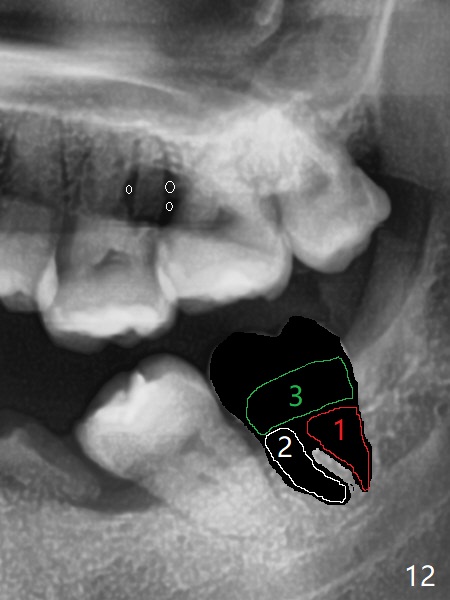

矫正器放置后一个月,正好有充裕时间,匆忙研究全景片(最好CT),好像左上6近中间隙大,近中颊侧,远中腭侧似乎是种植位点(图一:白圆圈),植入越高越宽,不容易伤及邻牙牙根。但是微型植体种植原则是必须种植在角化龈,减少炎症(以前不明白为什么)。当植体在移动牙龈植入时(图二:白箭头),牙龈浮起来,估计非角化牙龈也不能与植体产生紧密结合。取出后,完全可以在6近中颊侧角化龈植入,但是仔细检查发现远中颊侧角化龈更宽,所以在那里扎根(图二:黑箭头),因此腭侧就得选择近中(图三)。微型植体可以即刻使用,power chains常滑脱,压迫牙龈,在这个病例很可能进入远中牙间隙,所以需要在远中边缘嵴加树脂(图四,五:* (1.6x8mm))。第二天远中颊侧植体松动,取出后,插入2x10毫米一段式植体,仍然松动(图六)。CT显示植体下缘穿破牙槽骨(图七,骨质吸收严重与图八近中牙槽骨高度对比)。如果在近中颊侧重新植入微型植体,必须使用6毫米长植体(图九),所以最好在远中颊侧重新植入(图十:红色),缺损区(黑色)植骨。在使用14 niti时,左下7松动,病人同意拔除8,以后后推7,然后6种植(图十一:(左上8已拔除(x))),同时左上6远中植骨,左下8远中牙槽窝放置浸泡PRF液体胶原塞(图十二:1),近中牙槽窝粘性骨粉(2),最后牙槽窝上部PRF膜(3),PGA缝线。可能需要Cytoplast。